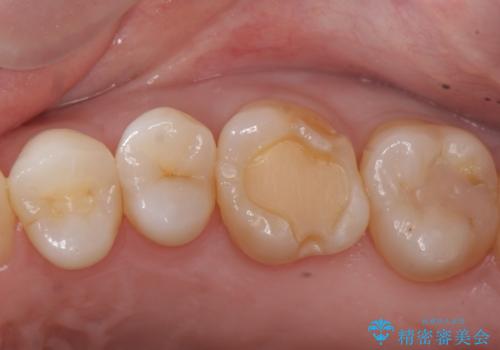

検診で虫歯を発見。

- 昔他院で虫歯治療をしたところが虫歯が再発したとのことで来院。

古い材料(プラスチックの樹脂)をとり、拡大鏡下で虫歯を全て取り除き、

ゴールドインレーにて治療しました。